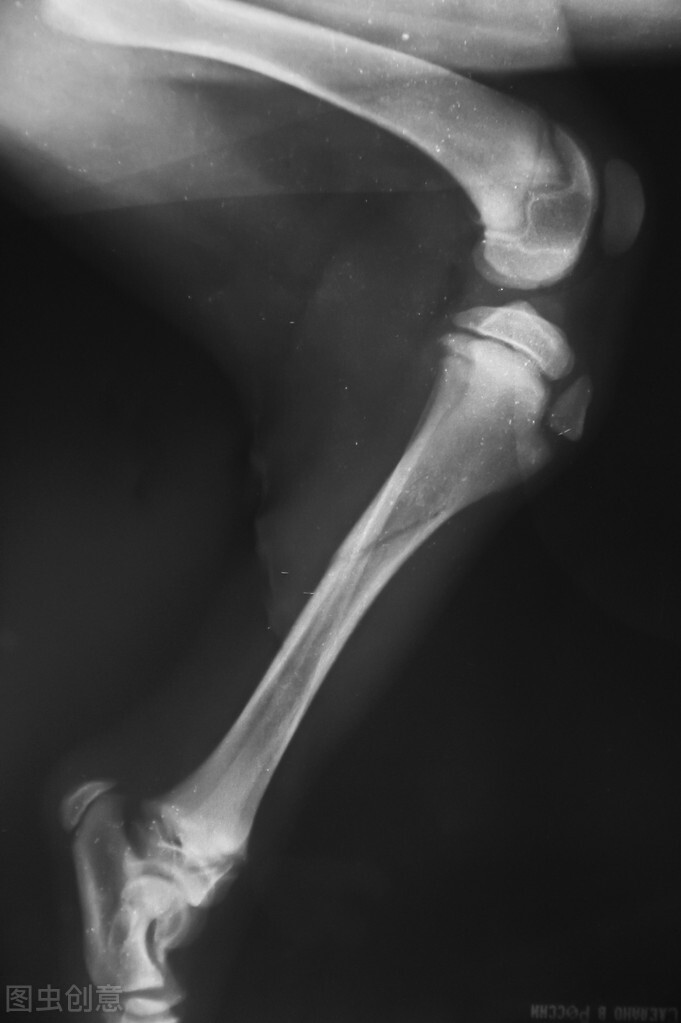

狗比人类更容易患关节疾病,动物需要每天使用关节,软骨表面不断磨损,最后会造成关节炎。

狗和猫患关节炎的早期症状:站立缓慢,跑步和跳跃不灵活,一瘸一拐;经常有鸣叫、哀号;关节疼痛、僵硬、肿胀、类型和功能障碍,常伴有继发性滑膜炎,严重者甚至瘫痪。

如果有以下症状,基本上可以判断狗有关节炎。如果不容易把握,可以带狗去宠物医院诊断。

1.狗醒来后,活动总是僵硬的,一个多小时后才恢复正常。

2.检查狗的身体,至少两个关节肿胀。

3.爪关节肥胖肿胀。

4.所有肿胀部位都有一定的对称性。

5.任何动作,即使是吃饭,也会有轻微的颤抖。